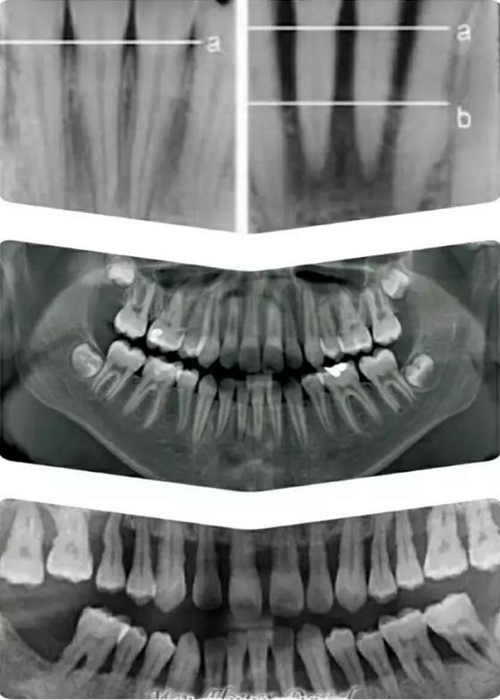

如上圖所示。 牙周這個詞或許有點陌生,它指的是牙齒周圍,包埋著牙根的硬質(zhì)的牙槽骨,和覆蓋其上肉眼可見的粉色牙齦。

牙槽骨對牙齒起主要固定支撐作用,并且一般只能在X 光片上顯示;牙齦是保護牙槽骨的第一道屏障。

有圖有真相。上面這組圖片,自上而下從左至右,顯示了人類健康牙齒,患牙周病后,未加治療控制,以致病況越來越嚴(yán)重,最終牙齒逐漸脫落的過程。

牙周病也稱牙周炎,是包繞牙齒周圍的牙齦和牙槽骨因發(fā)生炎癥而萎縮,對牙齒逐漸失去固定支撐作用以致牙齒逐漸松脫的一類最常見牙齒疾病。

在上圖X光顯示下,牙槽骨從正常水平 a 線萎縮到了b 線(中圖為正常全口X光牙片,最下圖為全口重度牙周病X光片),以至不能再固定支撐牙齒,就象埋在電線桿周圍的土被挖掉,電線桿只能逐漸倒伏一樣。